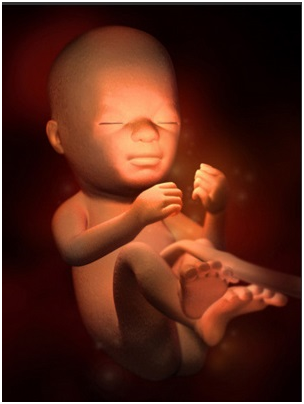

怀孕第8周如果还没检查过的准妈妈,这周一定要开始第一次产前检查啦!胎儿的胚胎器官已经开始具...

怀孕第8周如果还没检查过的准妈妈,这周一定要开始第一次产前检查啦!胎儿的胚胎器官已经开始具... -

怀孕第10周在怀孕前,你的子宫大概和小香梨一样大,但现在已经长到一个大橙子那么大了。这段时间...

怀孕第10周在怀孕前,你的子宫大概和小香梨一样大,但现在已经长到一个大橙子那么大了。这段时间... -

怀孕第11周11周开始,你的早孕反应开始慢慢减轻,现在你也不必为流产过多担心了。为了生个健康...

怀孕第11周11周开始,你的早孕反应开始慢慢减轻,现在你也不必为流产过多担心了。为了生个健康... -